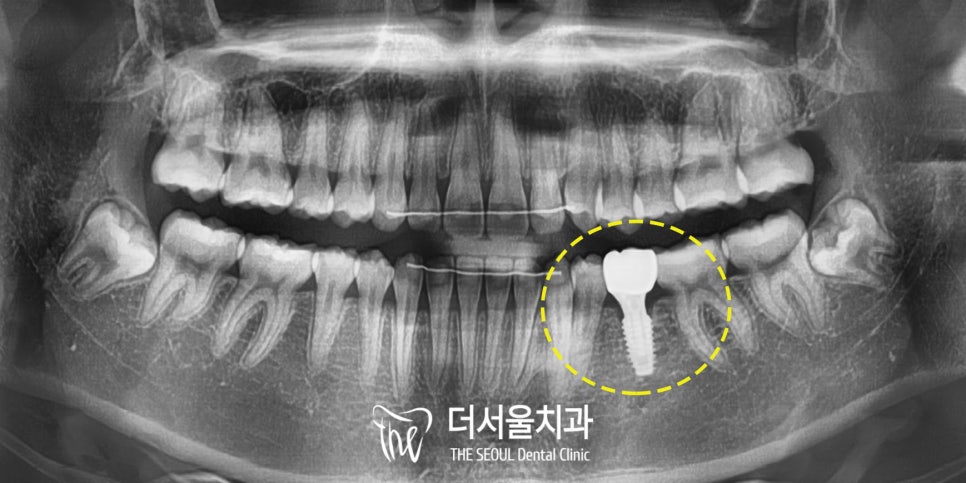

표시된 치아의

뿌리가 짧고 작은 것을 볼 수 있죠?

이를 무치증이라 부르며

28개 치아 중 1개 이상이

선천적으로 없는 경우입니다.

픽스처 식립 후에는 3차원 CT를 이용하여

올바른 위치에 곧게 식립되었는지 확인합니다.

건강한 치조골 사이에

단단하게 심어진 게 보이시나요?